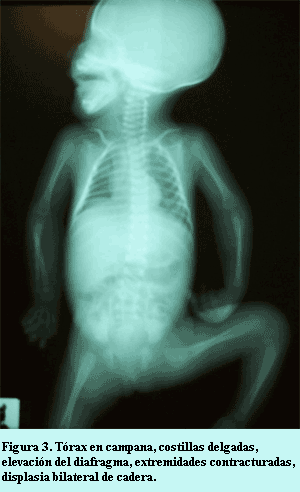

Laboratorio: biometría hemática sin alteraciones, gasometría y electrolitos en niveles normales; química sanguínea: glucosa 70 mg/dL, urea 22 mg/dL, creatinina 0,5 mg/dL, amonio 90 mg/dL, creatinquinasa sérica 350 U/L, tamizaje metabólico negativo. Radiológicamente se encontró tórax en campana, cuerpos costales delgados y finos, silueta cardíaca ovoidea con levantamiento del ápex cardíaco por crecimiento de ventrículo derecho, situación elevada del diafragma y sombra hepática incrementada; extremidades superiores mostrando flexión moderada de mano sobre antebrazo y brazo en ambos lados, y las inferiores con flexión de pierna sobre muslo, displasia de cadera bilateral (figura 3). El electrocardiograma mostró ritmo sinusal, frecuencia de 140 por minuto, eje 120º, crecimiento de ventrículo derecho, y el ecocardiograma con hipertrofia leve del tabique ventricular sin obstrucción del tracto de salida del ventrículo izquierdo, comunicación interauricular pequeña tipo foramen oval. La paciente tuvo evolución desfavorable complicándose con convulsiones tónicoclónicas generalizada causadas por encefalopatía hipóxico-isquémica, la tomografía de encéfalo mostró edema cerebral difuso e hipodensidades en corteza cerebral; finalmente presentó arritmia y falla cardiaca congestiva venosa; murió por falla respiratoria severa al mes de edad.

La posibilidad diagnóstica se redujo a distrofia miotónica que es la forma más frecuente de las distrofias musculares, con una prevalencia de 1/20.000 individuos adultos; se caracteriza por debilidad progresiva muscular (distrofia) y espasmos musculares o rigidez con dificultad para el relajamiento muscular después de contracciones repetidas (miotonía). La afección congénita es una enfermedad sistémica grave que puede afectar ambos sexos, y se presenta en hijos de madres con distrofia manifiesta o sutil (7); resulta difícil de diagnosticar durante la etapa neonatal, debiendo constatarse los criterios clínicos de Wesstrom: hipotonía, facies miopática, pobre control de la cabeza, debilidad y atrofia muscular, problemas para la alimentación y dificultad respiratoria (8); existen, además, otros hallazgos complementarios como son: parálisis diafragmática, costillas delgadas y deformación esquelética como pie equino (9). El caso tenía clínicamente todos los datos (10) y además la madre, aunque no mostraba sintomatología de la enfermedad, cuando se le ordenaba abrir y cerrar el puño en forma repetida o sacudir las manos presentaba respuesta fatigada, orientadora de distrofia miotónica subclínica. Los padres no permitieron biopsia muscular de la paciente que hubiera identificado fibras en anillo con miofilamentos periféricos, núcleos en disposición central y masas sarcoplásmicas. Se dio consejo genético, pues es un problema hereditario que muestra anticipación, que expresará mayor severidad fenotípica en hijos subsecuentes, siendo la posibilidad de recurrencia mayor del 50% en cada nuevo embarazo (11).